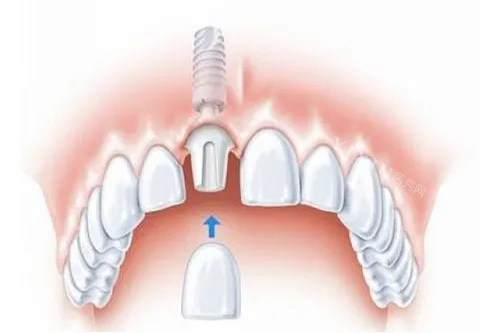

医院的医生团队实力强劲,由院长苏永医生领衔,尤其擅长全口种植牙、小创口种植牙、即刻种植牙等高难度技术。苏永医生运用3D导板定位技术,将种植体植入误差控制在0.1毫米以内,配合All-on-4技术,需要4-6颗种植体就能改善全口咀嚼功能,尤其适合牙槽骨萎缩的老年人。此外,医院的医生团队还会定期参加学术交流和培训,不断提升技术水平。

新天元口腔医院的诊疗科目非常齐全,涵盖了口腔科的各个领域。在种植牙方面,医院提供即刻种植、小创口种植、全口半口种植等多种方案。牙齿矫正也是医院的特色项目之一,医生会根据患者的具体情况,结合面部美学设计专属方案,提供金属托槽矫正和隐形矫正等多种选择。此外,医院还擅长儿童口腔保健,提供窝沟封闭、涂氟防蛀、乳牙早失间隙管理等服务。

新天元口腔医院的价格透明合理,种植牙单颗5000元起,矫正8800元起,明码标价无隐形消费。此外,医院还提供多期付款选择,学生党、上班族都能根据预算灵活选择方案。